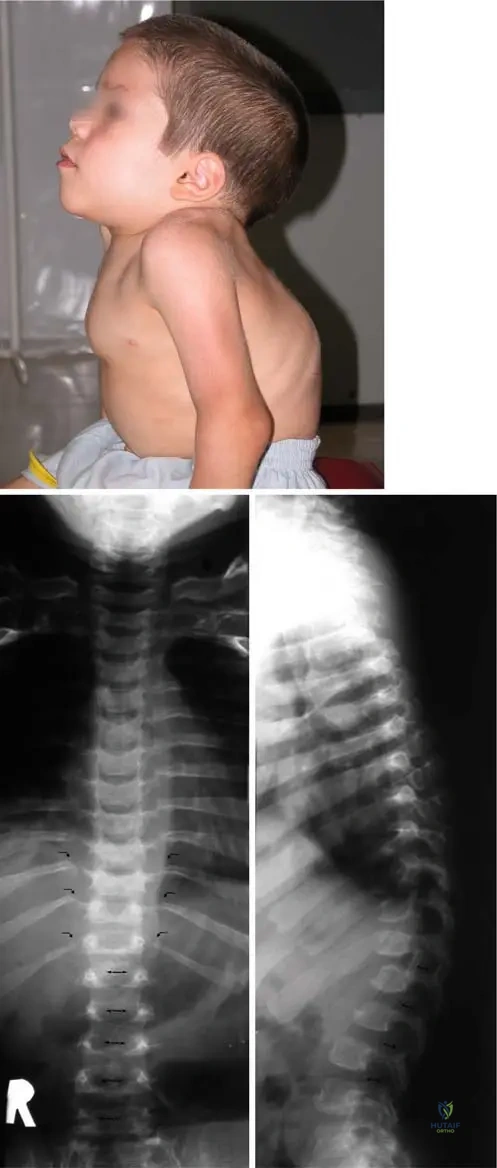

Rationale: The clinical context for Fig. 1.39a states, "Characteristic features for Hurler syndrome are the dorsal kyphosis (a)..." Lumbar lordosis is incorrect; the text specifies dorsal kyphosis.

Correct Answer: A

View Answer & Explanation

Rationale: The clinical context for Fig. 1.39c states, "Characteristic features for Hurler syndrome are... with the very typical dorsolumbar gibbus (c)." Lumbar scoliosis is incorrect; the text specifically identifies a dorsolumbar gibbus as the typical deformity.